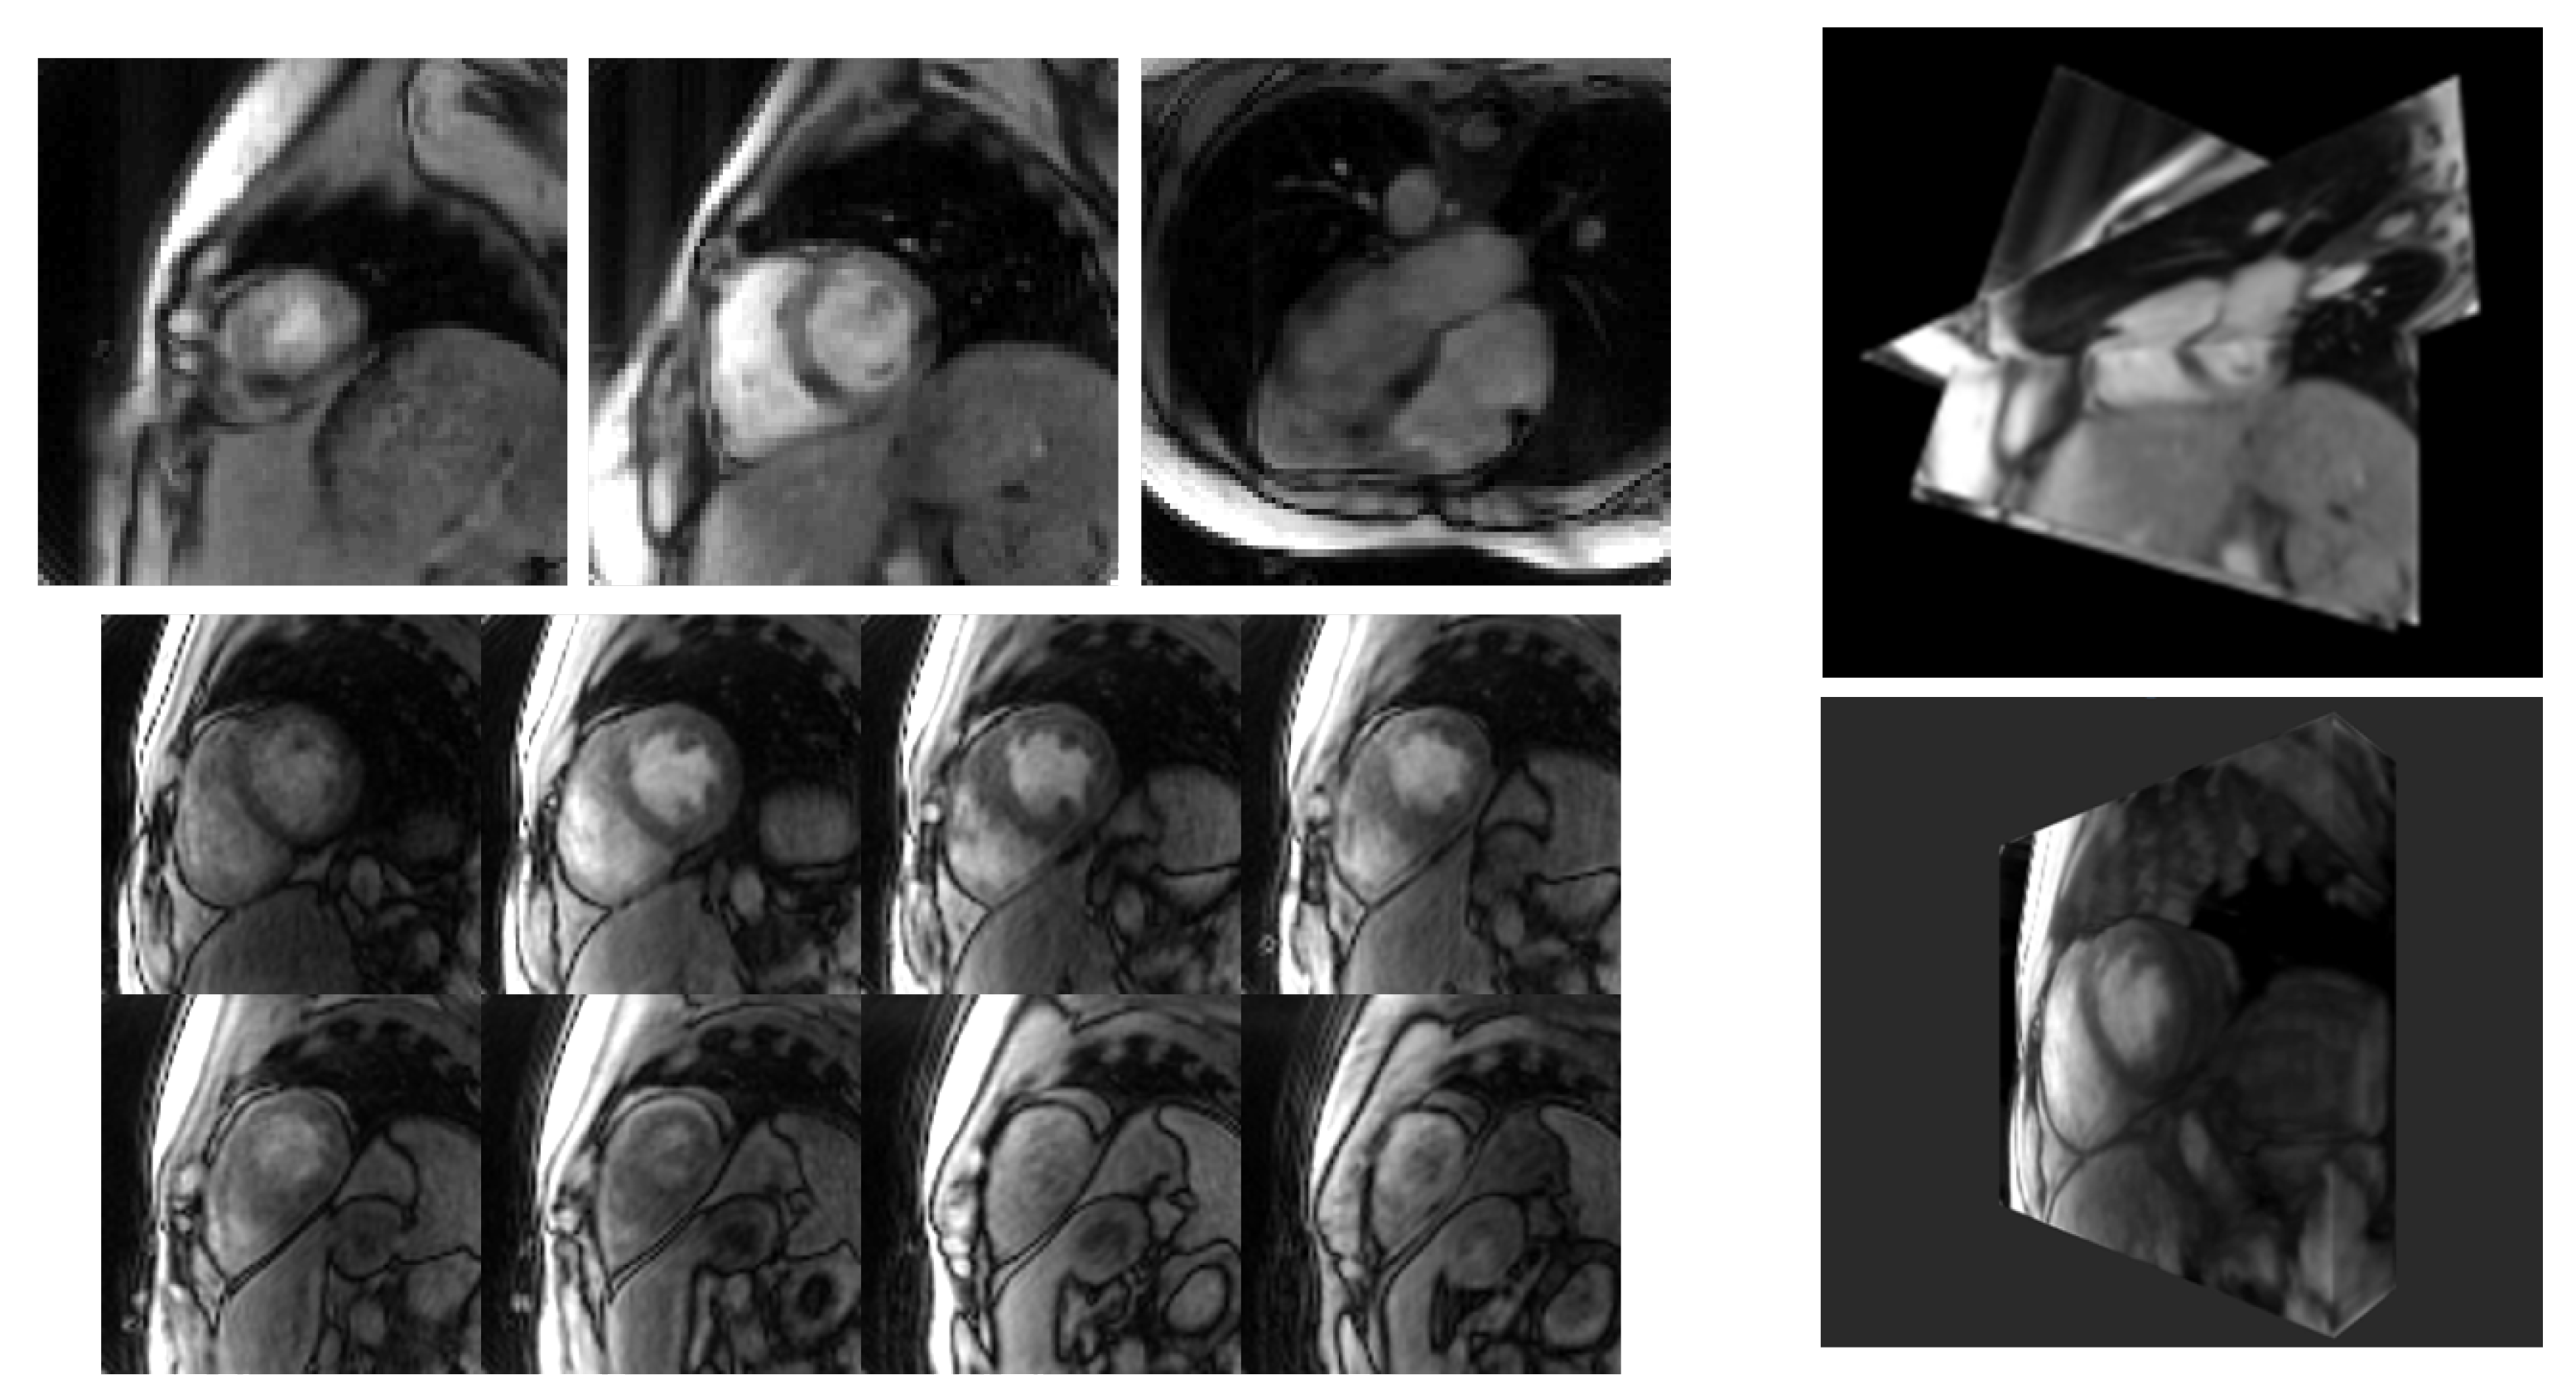

3. Results